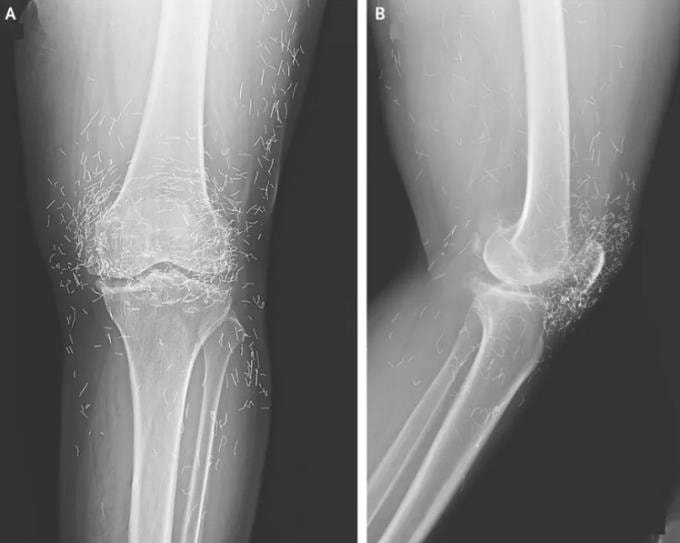

Một phụ nữ 65 tuổi tại Hàn Quốc nhập viện trong tình trạng hai đầu gối đau nhức dữ dội dù đã điều trị qua nhiều phương pháp. Trước đó, bà bị thoái hóa khớp gối nhưng đã ngưng dùng thuốc Tây y do tác dụng phụ gây đau dạ dày. Bà dùng liệu pháp châm cứu với tần suất nhiều lần mỗi tuần.

Kết quả chụp X-quang khiến các bác sĩ kinh ngạc khi phát hiện hàng trăm đốm kim loại nhỏ bao vây kín khớp gối bệnh nhân. Đây là những đoạn chỉ vàng vô trùng được chủ ý để lại trong mô cơ trong quá trình châm cứu nhằm tạo kích thích giảm đau liên tục. Báo cáo không đề cập việc những sợi chỉ vàng có được lấy ra khỏi cơ thể bệnh nhân hay không nhưng trong các trường hợp trước đây, chúng thường được để nguyên tại chỗ. Tuy nhiên, việc không loại bỏ các sợi chỉ vàng vẫn tiềm ẩn rủi ro hình thành nang do các dị vật này gây ra.

Trong báo cáo về ca bệnh trên, các bác sĩ cho biết châm cứu bằng chỉ vàng vốn được sử dụng phổ biến tại châu Á để điều trị cả thoái hóa khớp và viêm khớp dạng thấp. Tuy nhiên, không có bằng chứng nào cho thấy phương pháp đó thực sự hiệu quả, thậm chí, một số trường hợp còn có thể gián tiếp làm bệnh trầm trọng hơn do khiến bệnh nhân lỡ mất cơ hội được điều trị đúng cách và kịp thời.

Ngoài ra, các sợi chỉ này có thể di trú bên trong cơ thể và những mảnh vụn của chúng có thể làm tổn thương mô lân cận. Chuyên gia y tế cảnh báo những sợi chỉ vàng được đưa vào cơ thể khi châm cứu có thể gây khó khăn cho việc đọc kết quả X-quang. Nhiều chuyên gia khác cũng cho rằng việc cấy chỉ vàng khiến bệnh nhân không thể chụp MRI (cộng hưởng từ) do nguy cơ kim loại bị dịch chuyển và làm tổn thương các động mạch.